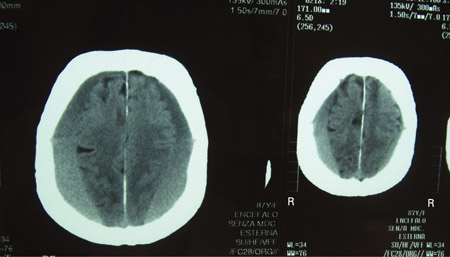

Subdural haematoma

CT scans of the brain of an 80-year-old man with a gait disorder and a progressive cognitive impairment dating back about 6 months, showing a bilateral chronic subdural haematoma up to the convexity

Adapted from BMJ Case Rep. 2009;2009:bcr06.2008.0130